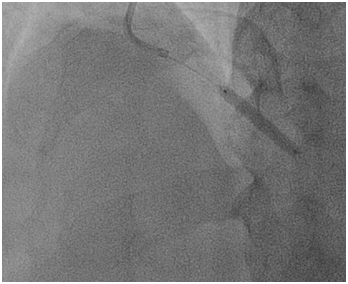

A 66-year old male with long standing history of type 2 diabetes, hypertension, dyslipidaemia and ischemic heart disease with prior history acute myocardial infarction treated with primary PCI to LAD with 3.0x22 mm drug eluting stent. Came for a staged PCI for a significant proximal RCA lesion. Following obtaining an informed consent and reload with 300 mg of Plavix. Right radial approach was selected patient received 7000 units of heparin. A 3DRCguidingcatheter was used to intubate the RCA following failure to engage with Judkin 4 guiding catheter, BMW wire advanced all the way to the distal end of RCA, lesion predilated by2.5x15mm compliant balloon to 12 atmospheres (Figure 1). A 3.5x 22mm Xience expedition stent was placed across the lesion under fluoroscopy. It was noted that the guide was not stable. It was decided to deploy the stent with the first fluoroscopy the stent appeared to have dislodged into the ascending aorta with the wire (Figure 2). Now the stent with an inflated balloon the guiding catheter and the wire all hanging in the ascending aorta. The initial decision to remedy this was to carefully and slowly withdraw the entire system along the course of the subclavian system and deploy the stent in a safe spot (Figure 3). But because of tortuosity it was thought to snare the entire system through a large femoral sheath. An 8 Fsheath was inserted into the right femoral artery and a 6 F ensnare system taken to the ascending aorta and grabbed the inflated balloon (Figure 4) and stent slowly moved down into the abdominal aorta under fluoroscopy. Then the balloon was deflated slowly and the snare tightened across the stent (Figure 5) and taken outside the body through the 8 F sheath (Figure 6) post snare femoral angiogram showed no injury to the femoral artery and a successful snaring of the dislodged stent. Patient was brought at alater date for a successful direct PCI to the RCA. This time the guide selected was an Amplatzer 0.75 (Figure 7).

Figure 4 Capturing the dislodged stent and inflated balloon with ensnare system.